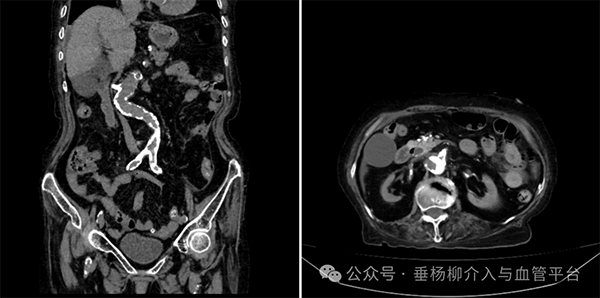

结果出来了,消化系统看起来并没有大问题,但有一条线索引起了医生们的注意:主动脉及分支动脉硬化非常严重,血管外科医生满新贺医生仔细看了看片子,还发现了更隐蔽的问题——陈阿姨的腹腔干动脉和肠系膜上动脉竟然严重狭窄,有的甚至闭塞了!

严重钙化的的腹主动脉和肠系膜上动脉